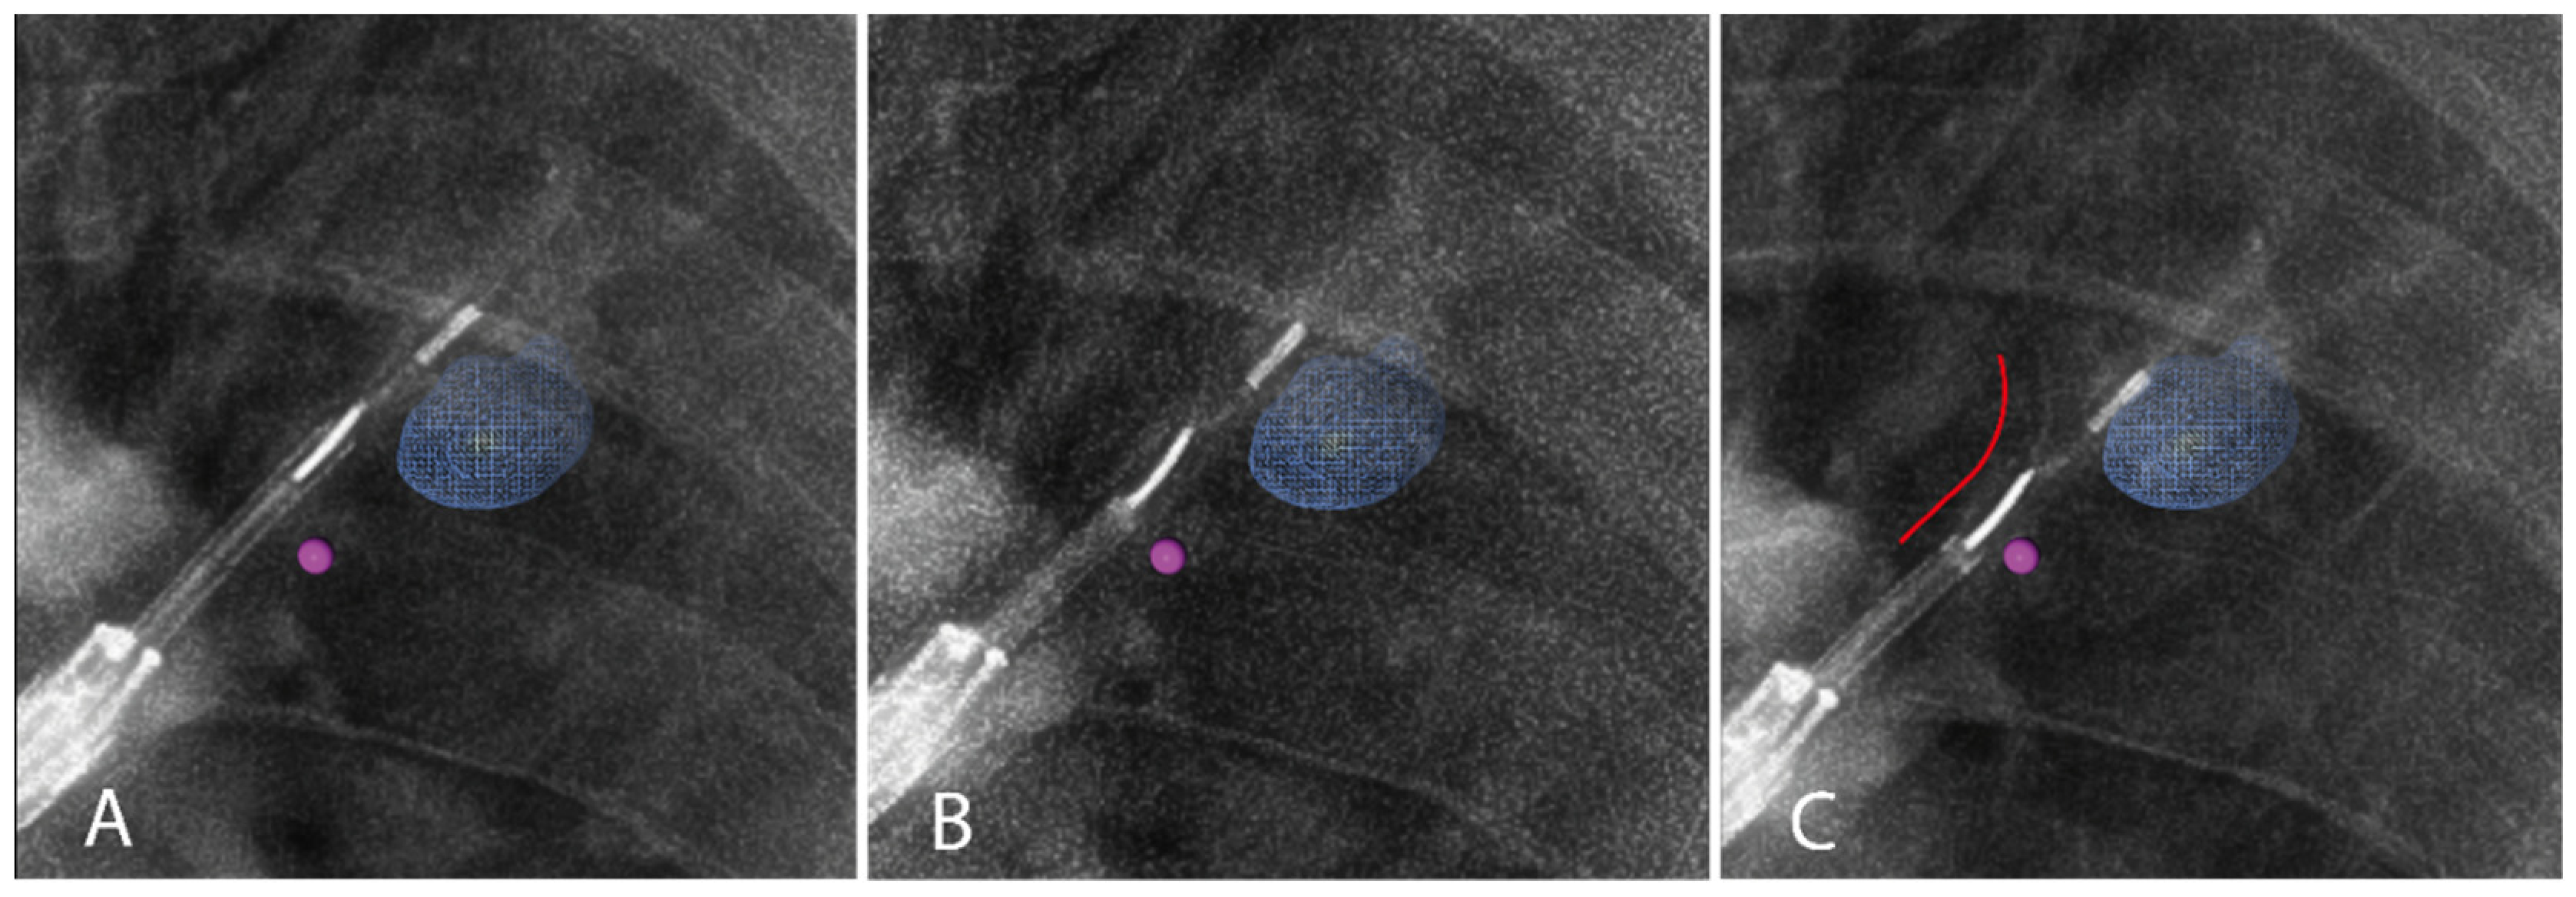

3.2.2. Iodinated Contrast Injection

| Leakage visible on fluoroscopy, n (%) | 4 (26.7%) | ||